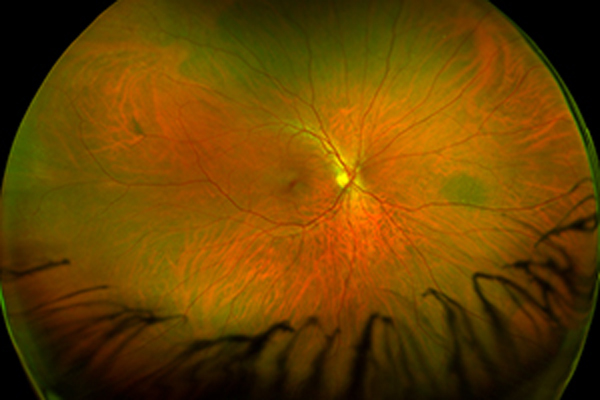

Fluoreszeinangiographie

Nicht Proliferative Retinopathie – Augenärztliche Gemeinschaftspraxis | Dr. Heuring, Dr. Jung & Kollegen

Ausgeprägte nicht proliferative Retinopathie mit ausgeprägten Fettablagerungen